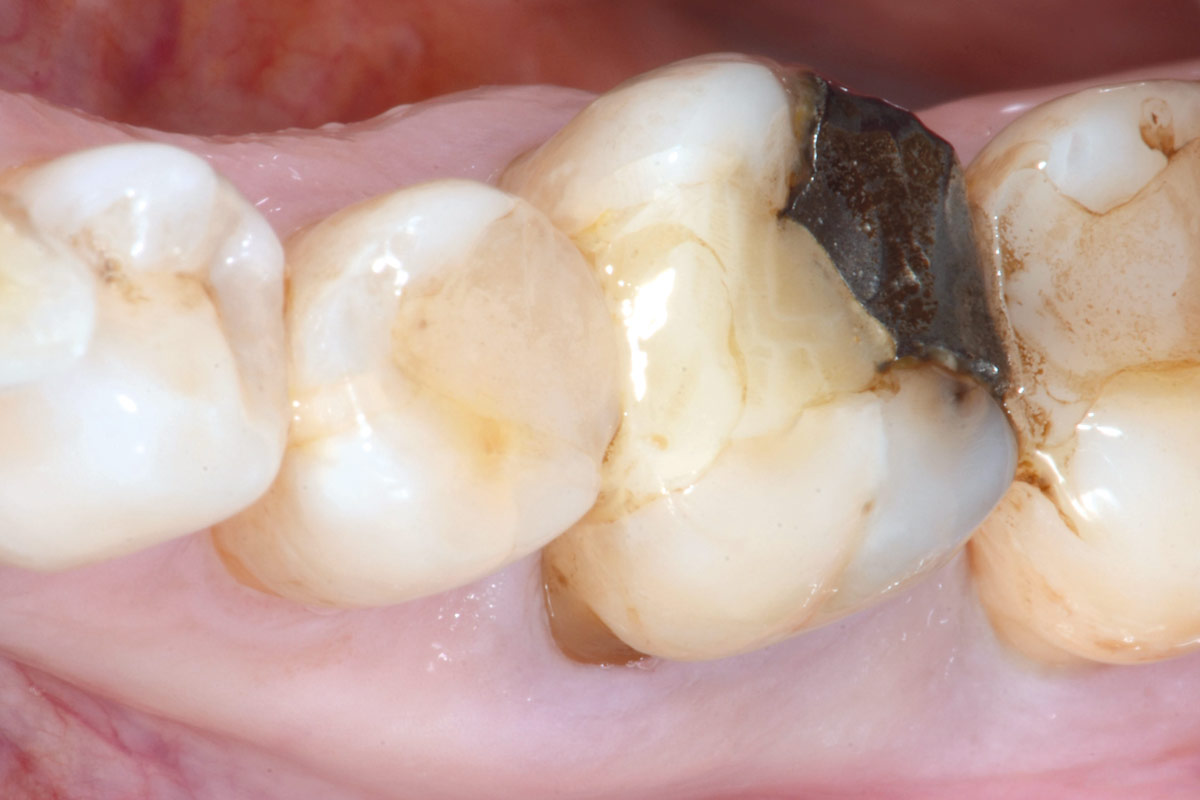

Clinical situation before extraction and implantation